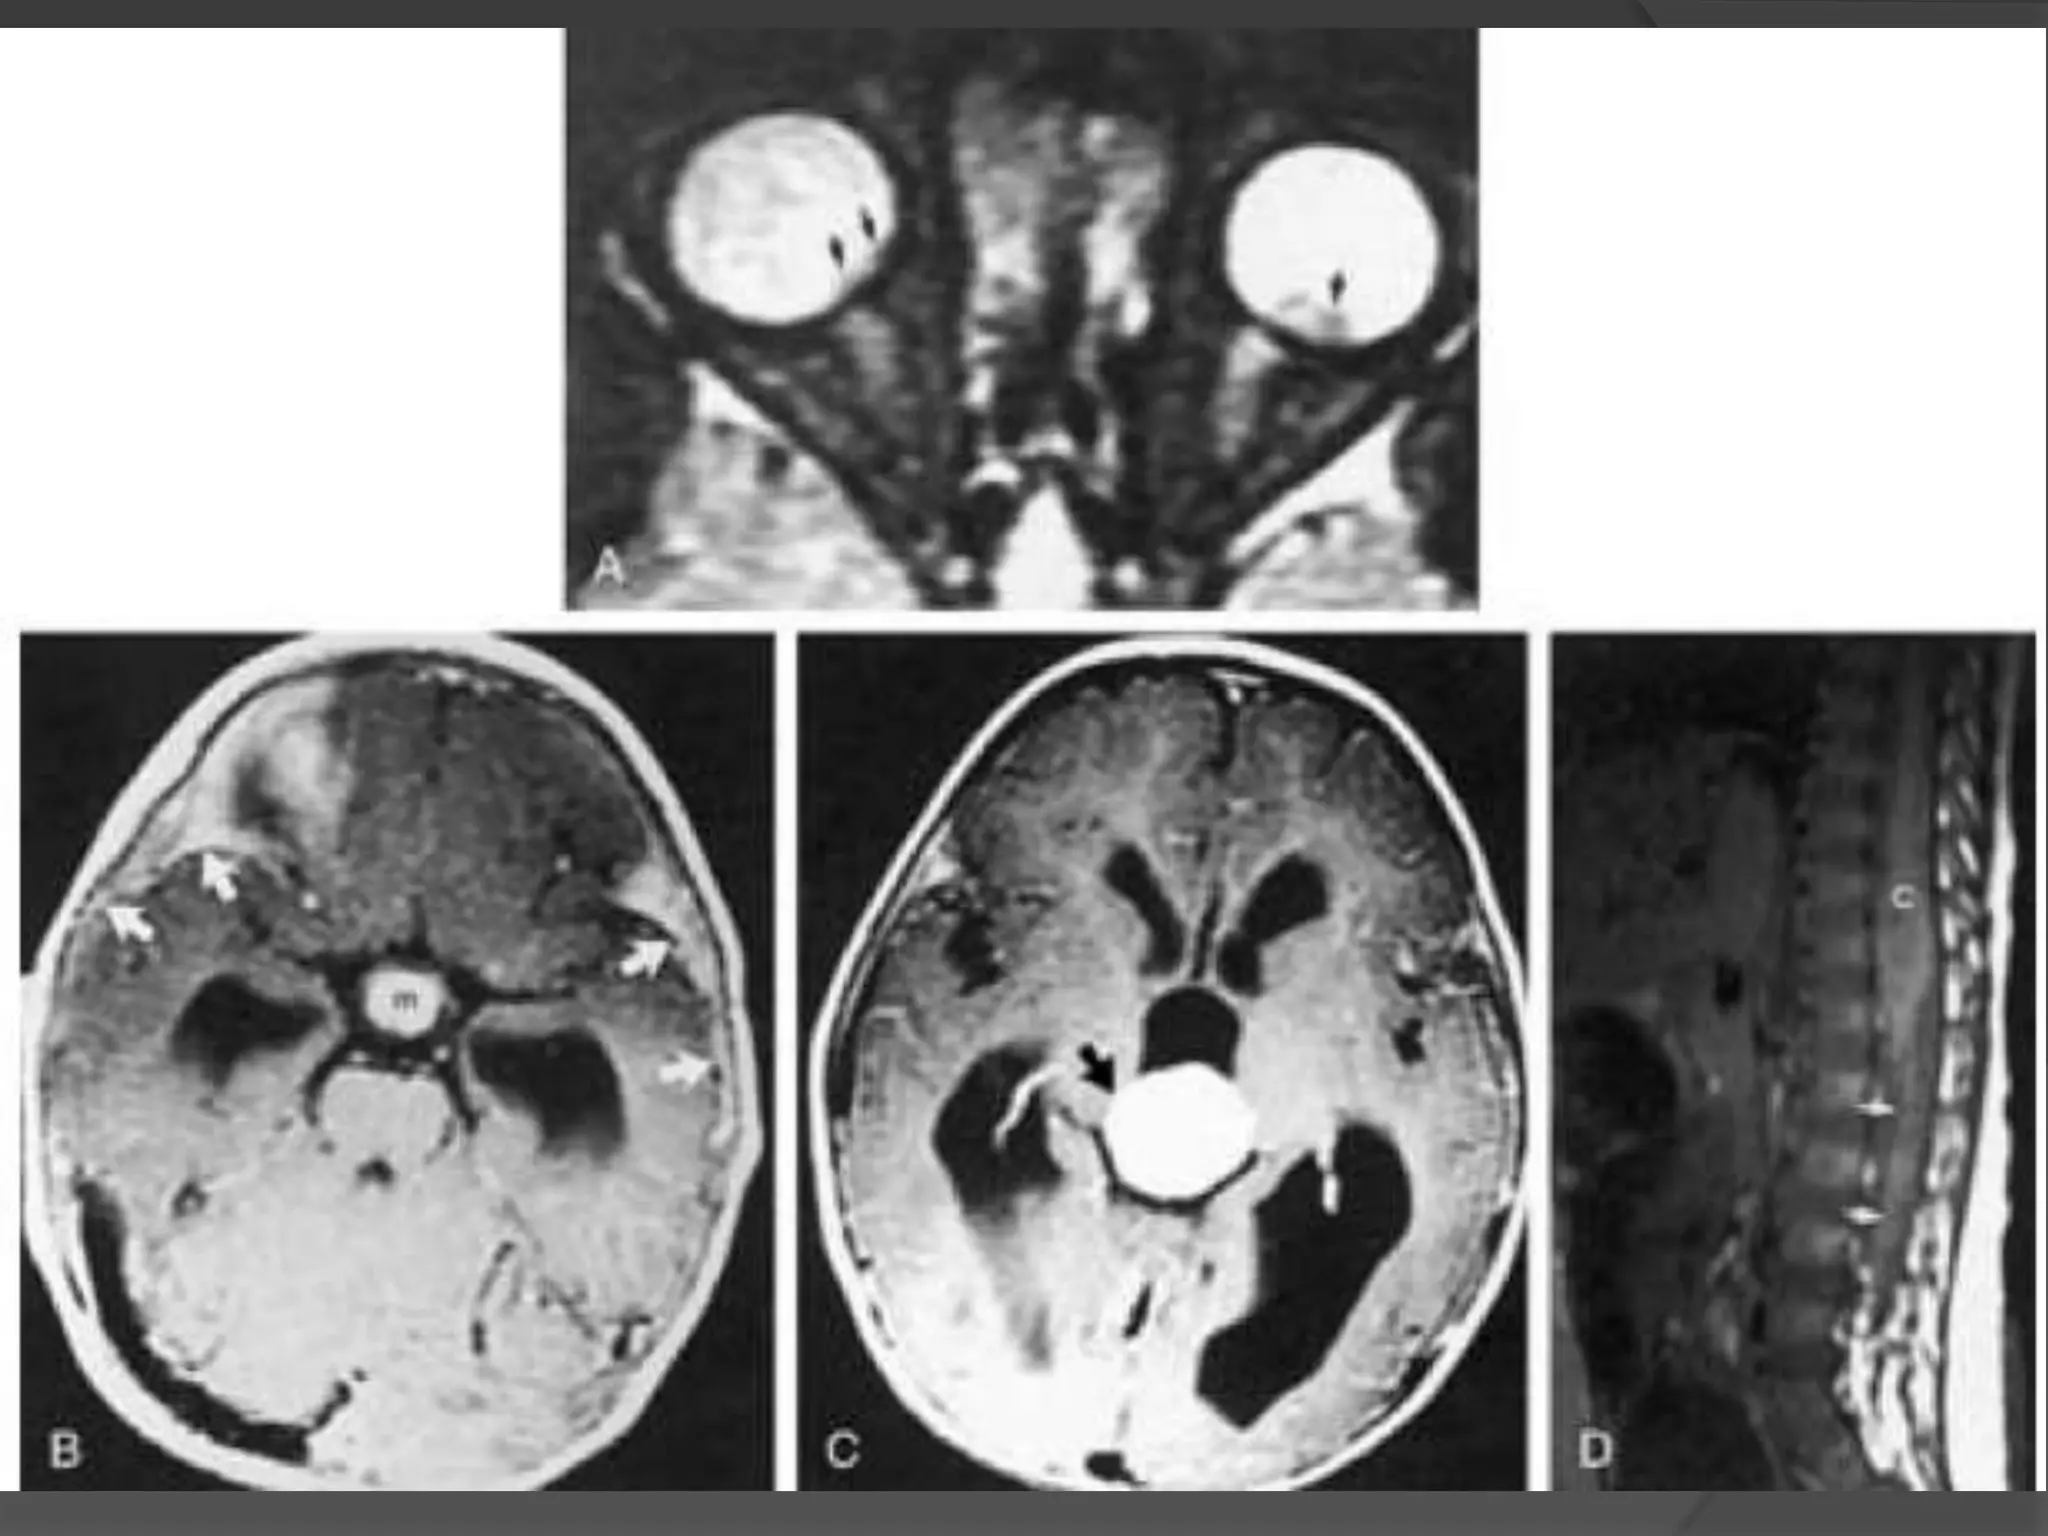

• #8 Colobomatous cyst. A, Axial CT scan shows bilateral microphthalmia and a large cyst (C) separated from the right globe by a band of enhancement (arrows), which is related to abnormal gliotic tissue. B, Anatomic section of an enucleated right eye. Note the small eye, large colobomatous defect, abnormal white tissues, gliotic tissues (G), and large cyst (C). Note the lens (L) and the optic nerve. C, Histologic section of an eye shows a large retinochoroidal coloboma (arrow), gliotic tissue (G ), cyst (C ), and lens (L).

• #9 Colobomatous cyst. Axial CT scan shows microphthalmic eyes with large cysts (arrows).